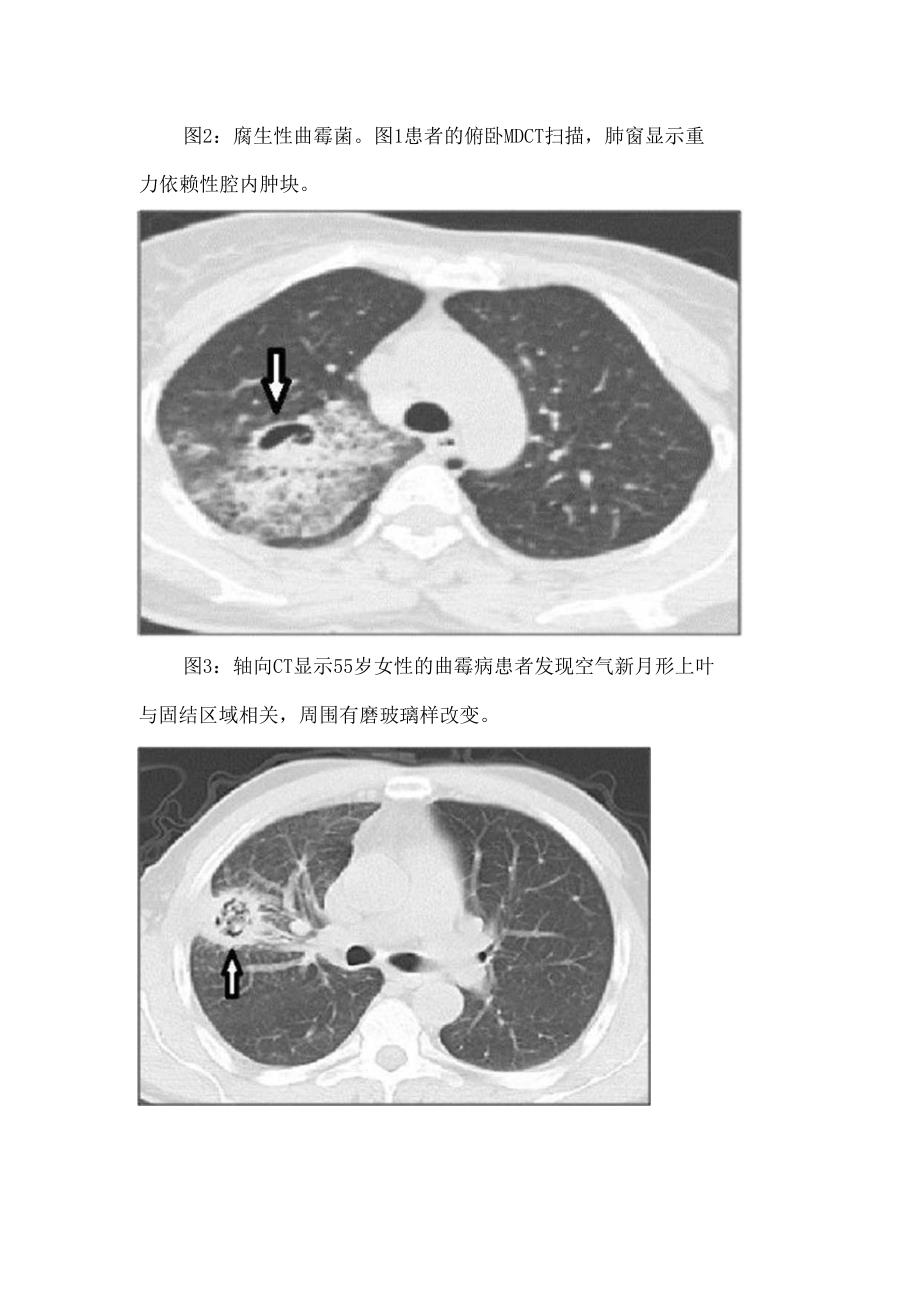

3、另一个常见特征是腔壁和邻近胸膜增厚。3、这种真菌球可能是移动的。图1:腐生性曲霉菌。肺窗仰卧MDCT扫描显示重力依赖性腔内肿块。图2:腐生性曲霉菌。图1患者的俯卧MDCT扫描,肺窗显示重力依赖性腔内肿块。图3:轴向CT显示55岁女性的曲霉病患者发现空气新月形上叶与固结区域相关,周围有磨玻璃样改变。图4:轴位CT显示右下叶的团块,中央区域为空洞,考虑诊断为曲霉菌,术后诊断为肺癌。图5:矢状图显示了与支气管扩张相关的右上叶曲管瘤。图6:胸片显示右上叶阴影,被空气新月包围:腔内的真菌球。图7:轴向和冠状CT扫描显示空腔内的真菌球,与支气管扩张和多发小叶中央结节相关。过敏性支气管肺曲霉菌病(ABPA)